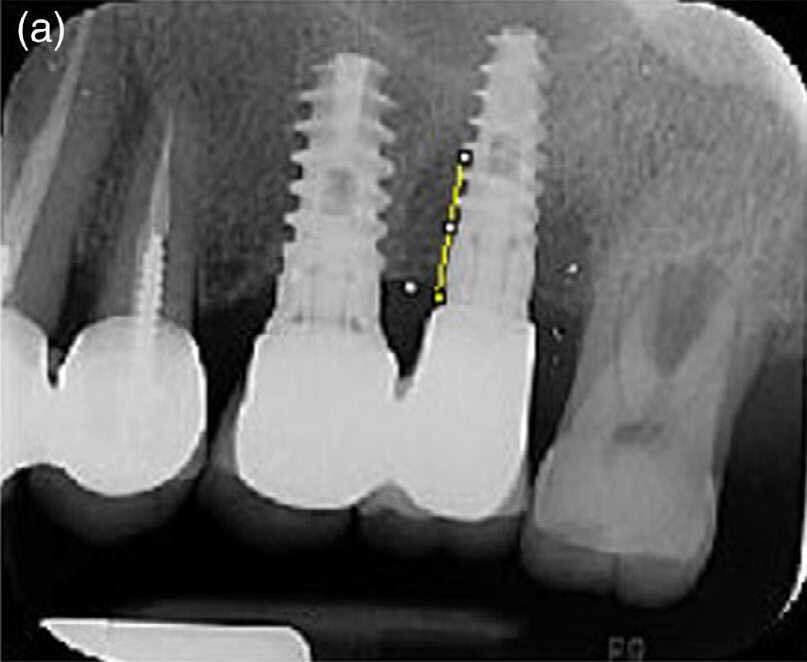

- La hauteur d’os (BL) a été mesurée entre la connexion implant-pilier et le fond du défaut osseux par un examinateur (O.G.), au début de l’étude et à T2, à l’aide d’un logiciel de traitement et d’analyse d’images (logiciel ImageJ, programme de traitement d’image écrit en Java, développé par les NIH [National Institutes of Health], Bethesda, Etats-Unis) (Fig. 2). Dans chaque radiographie, la longueur de l’implant fournie par le fabricant a été utilisée pour étalonner les mesures ≪ apico-coronaires ≫. La distance jusqu’au tissu osseux coronaire a été mesurée au niveau de la face mésiale et de la face distale de l’implant.

Des radiographies per apicales prises avant le traitement et 12 mois après le traitement n’étaient disponibles que pour un nombre limite d’implants (12 dans le groupe P et 15 dans le groupe M). L’analyse radiographique des mesures de hauteur osseuse n’a pas montré de différences statistiquement significatives entre les deux modalités de traitement (données non présentées/données sur fichier).